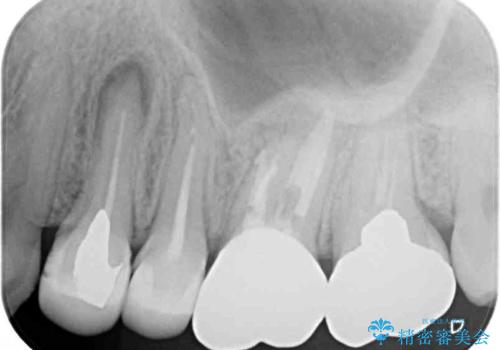

- 笑ったときに見てしまう上顎奥歯の銀歯を気にして来院された患者様です。

折角セラミッククラウンを装着するので、根管治療を行った後に補綴治療を行うこととしました。

他にも目立つ銀歯がありましたが、最も気にしている2本を優先して行うこととしました。

結婚式前にはクリーニングやホワイトニングを行い、その後他の歯を治療していく予定です。